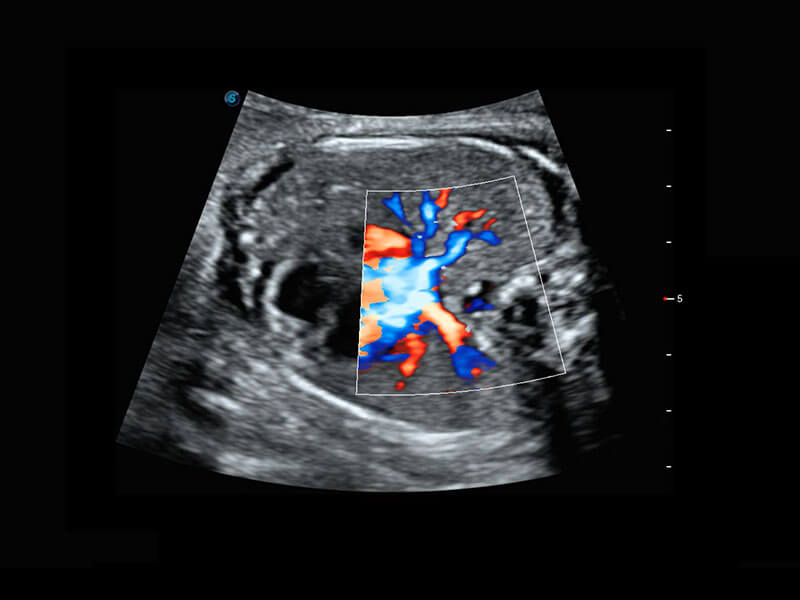

P60搭载一系列胎儿心脏成像技术,实现精细的胎儿心脏评估。

四腔切面

四腔心血流

右室双出口

胎心容积成像